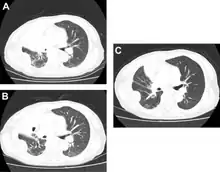

-

Docetaxel for non-small-cell lung cancer a) before b) tumor response after two cycles c) after 4 cycles

Docetaxel for non-small-cell lung cancer a) before b) tumor response after two cycles c) after 4 cycles -